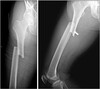

79

What pathology is present?

Galeazzi #

# What pathology is this describing? Fracture of the distal third of the radius, with posterior dislocation of the distal ulna